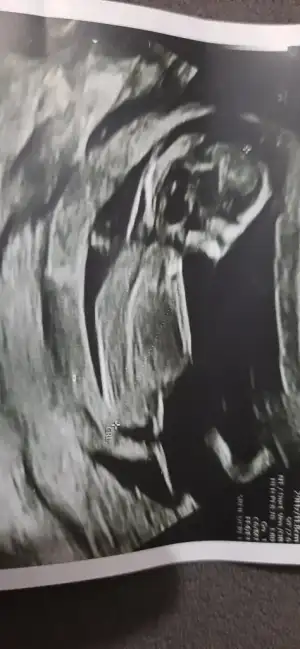

Aynen geçen hafta 13. Haftamdı ve doktorum perinatolog beyin lobları, kalbi, kalbin etrafını saran yapı, damarları, parmakları, midesi, damakları, dudakları her şeyi tek tek incelendi. Neredeyse omurunu ve kaburgalarını bile tek tek sayacaktı. Bu haftalar kontrol için cidden önemli ki görüşmenin sonunda ‘işte şimdi sevinip kutlayabilirsiniz’ dedi. Sonra da nifty için kan verdim salı kontrolüm var o zamana kadar sonuç da gelmiş olacak, inşallah o da iyi gelir ve ben birkaç gece de olsa huzurlu uyurum